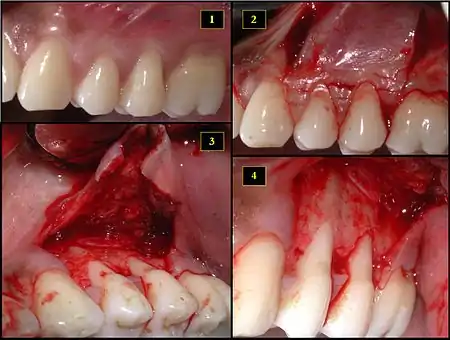

- Recipient site exhibits gingival recession on both premolars and first molar (molar recession is not an esthetic issue and will not be treated)

- Incisions prior to flap reflection

- Full thickness flap elevated

- Another viewpoint of the flapped recipient site